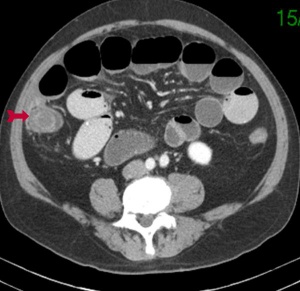

- במקצת מהחולים יימצא אוויר חופשי בדרכי המרה (תצלום 45.8).